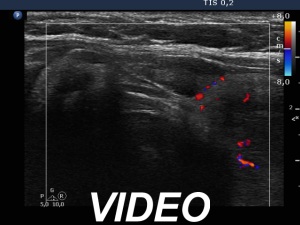

Second examination 3 years later (second, fourth and sixth rows of images):

Ultrasonography. Compared with the previous examination, both the number and the size of discrete lesions in the thyroid have increased.